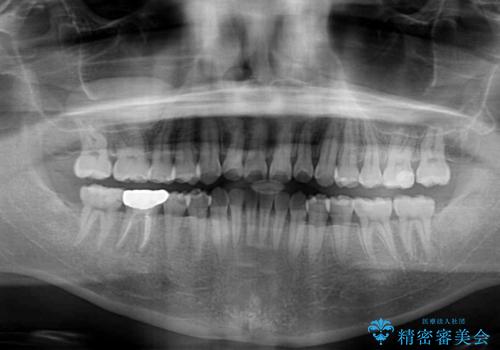

- 前歯のデコボコを治したいとのことで来院された患者様です。

できる限り楽して、短期間で治したいとのことで、ワイヤー装置にて矯正治療を行うこととしました。

- 治療期間

- 9ヶ月